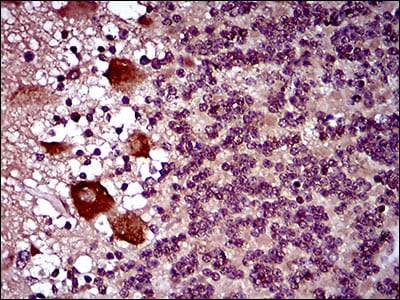

分类: 科研抗体货号: 30509别名: IRIS; PSCP; BRCAI; BRCC1; PNCA4; RNF53; BROVCA1; PPP1R53应用: IHC反应种属: Human